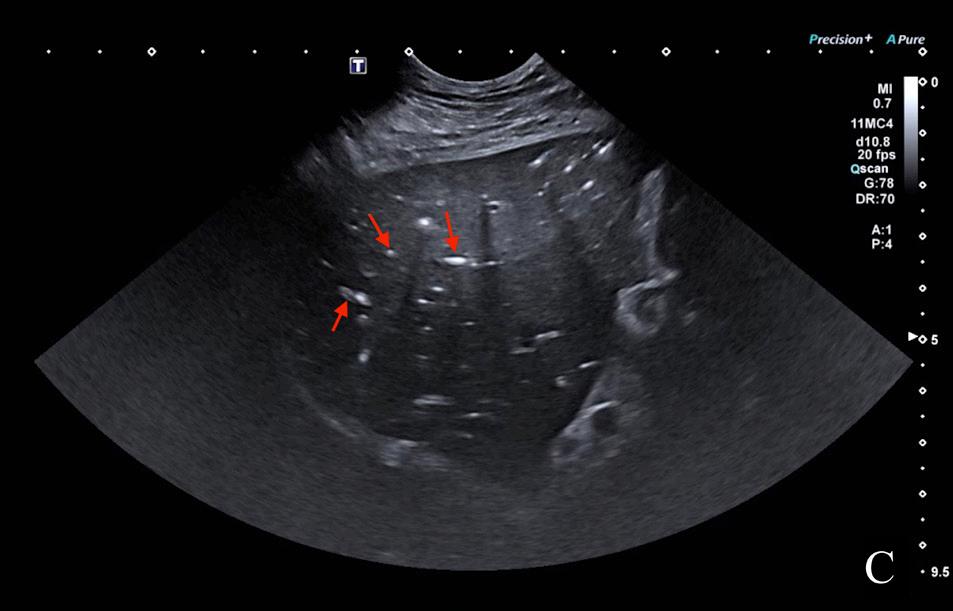

En el presente caso, se realizó una ecografía abdominal donde se identificó la presencia de una masa hepática, heterogénea y de bordes poco definidos, de

Figura 2. Imágenes ampliadas de las radiografías en proyección lateral izquierda (A) y ventrodorsal (B). Se observa la lesión de opacidad gas y bordes irregulares localizada en la proyección hepática, en su aspecto craneoventral y lateralizada a la derecha (flechas blancas). Se muestra otra lesión de opacidad gas, de menor tamaño respecto a la descrita, en la zona media del hígado (flechas moradas), que provoca un efecto masa (*) y genera un desplazamiento hacia caudal del antro pilórico y cuerpo gástrico (flechas negras). Caudoventral a la silueta hepática se observan pequeñas burbujas de gas libre compatible con neumoperitoneo (flechas azules).

8,2 x 6,1 cm, localizada en el aspecto ventral derecho y medio del hígado, con mineralizaciones diminutas y presencia de focos ecogénicos que provocaban artefacto de reverberación compatible con gas intralesional (Fig. 3A); así como otro nódulo hipoecoico de 2,8 x 2,7 cm (Fig. 3B). Además, en el aspecto craneal de los lóbulos hepáticos derechos, se encontró una lesión cavitada, con gas en su interior (Fig. 3B) y múltiples acúmulos de gas intravascular adyacentes a la lesión (Fig. 3C). También se observó un pequeño volumen de líquido libre ecogénico entre los órganos abdominales, gas libre y reacción peritoneal adyacente al hígado.

Se realizó una abdominocentesis ecoguiada que confirmó una peritonitis séptica. Con estos hallazgos, el diagnóstico presuntivo fue de dos abscesos asocia-

Figura 3. Imágenes ecográficas del parénquima hepático mostrando diferentes lesiones. (A) Se observa una masa hepática (*) con presencia de gas intralesional (flecha roja). (B) Lesión hepática con gas en su interior que produce artefacto de reverberación (flecha roja) y un nódulo hipoecoico y bien delimitado (*). (C) Se aprecian múltiples acúmulos de gas intraparenquimatosos a nivel intravascular (flechas rojas).